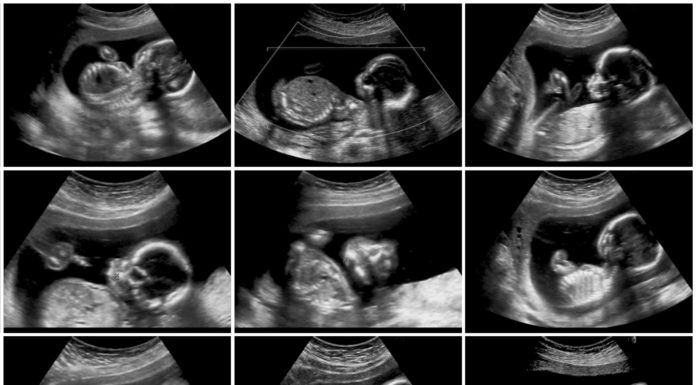

Slechts een minderheid van de zwangere vrouwen weet dat ze een prik kunnen krijgen om kinkhoest bij hun baby te voorkomen. En de...